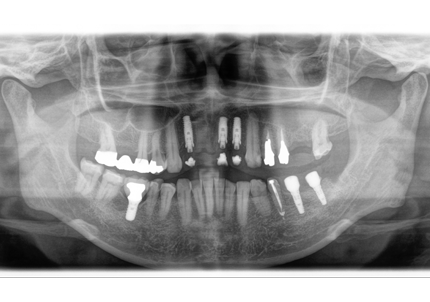

受傷時パノラマレントゲン(2018年5月17日)

初診日 : 2018年5月17日

治療計画 :

・右上3.1番 歯牙破折… インプラントブリッジ

・左上2番 歯牙破折…インプラントブリッジ

・左上1番 脱落…インプラントブリッジ

・右下1番 脱落…ブリッジ

【受傷時 2018年5月17日】

【受傷時 パノラマレントゲン】

【最終補綴物装着 パノラマレントゲン】